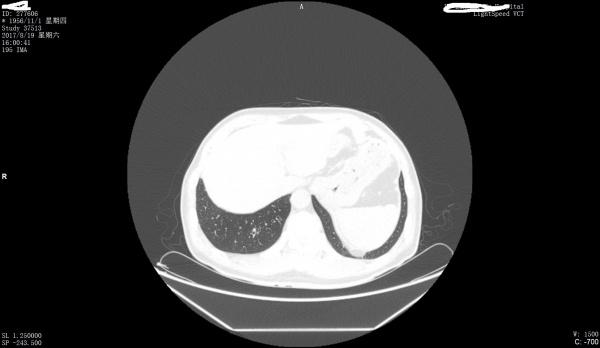

看看是否左膈肌出现胸腹膜裂孔疝

最好把纵膈窗也传一下